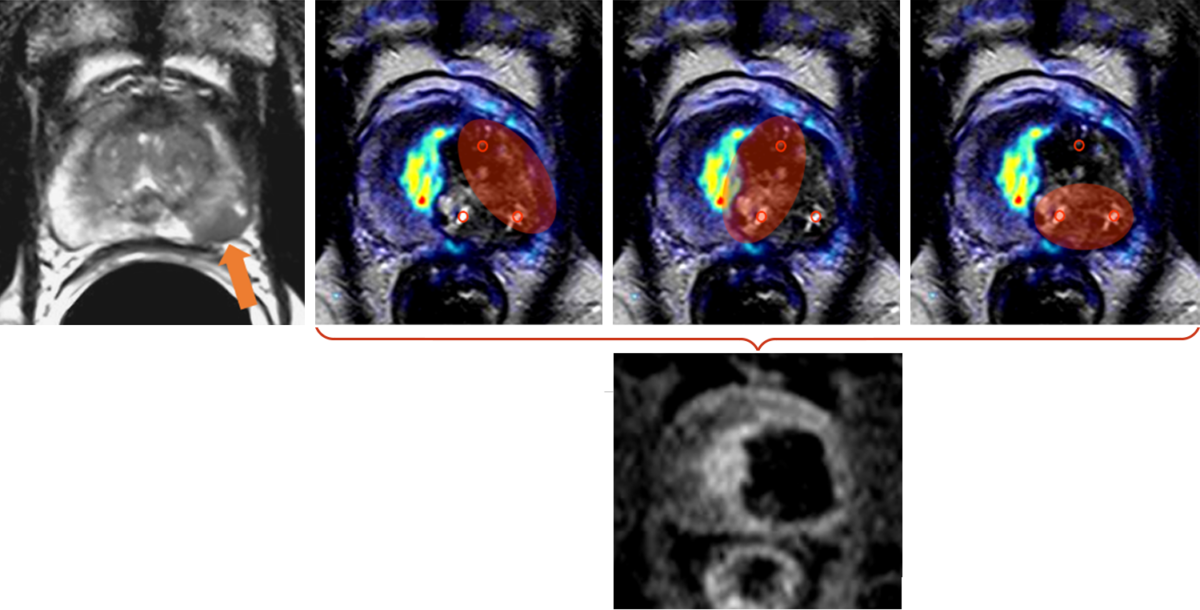

Je Elektrodenpaar wurde eine Ablationszone erzeugt (rote Ellipsen). Im Bild nach Kontrastmittelgabe ist die Ablationszone als avaskuläres Gebiet ohne Blutversorgung deutlich zu erkennen. Der PSA-Spiegel sank von 5,2 ng/ml vor der Behandlung auf 2,3 ng/ml nach der IRE und nicht auf Null, da der rechte Prostatalappen erhalten blieb. Dies ist typisch für fokale Therapien.

Die Behandlung erfolgte mit 5 Elektroden deren Positionen am Tag nach der Behandlung sichtbar sind (kleine schwarze Kreise). Je Elektrodenpaar wurde eine Ablationszone erzeugt (rote Ellipsen), insgesamt 9 einzelne Ablationszonen. Im Bild nach Kontrastmittelgabe ist die Gesamtablationszone als avaskuläres Gebiet ohne Blutversorgung deutlich zu erkennen.

Das Prostatagewebe wurde komplett zerstört, nur die Prostatakapsel ist erhalten, da sie weitgehen aus Bindegewebe besteht, das durch IRE nicht zerstört wird. Der PSA-Spiegel sank, wie nach einer Prostatektomie, auf 0 ng/ml.

PSA 11 ng/ml

PSA 0,0 ng/ml

Die Abbildungen zeigen die Behandlung eines Prostatakarzinoms Stadium T2c, N0, M0, Gleason-Score 8, bei einem 63-jährigen Mann. Das Karzinom hat sich über beide Prostatalappen ausgedehnt. Eine fokale Therapie unter Erhalt wesentlicher Anteile gesunden Prostatagewebes war in diesem Fall nicht mehr möglich.